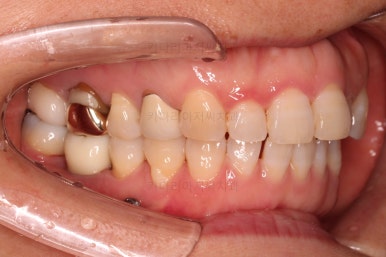

최종 사진을 보여드리겠습니다.

깔끔하게 마무리가 되었네요.

전후 비교입니다.

환자분도 치료에 만족하시어 미적으로 보기싫은 다른 금니들도 하나씩 교체하고 계신 중입니다.

이상 미니스크류를 이용하여 쓰러진 어금니를 연산동부분교정하고, 임플란트를 식립한 치료사례였습니다.